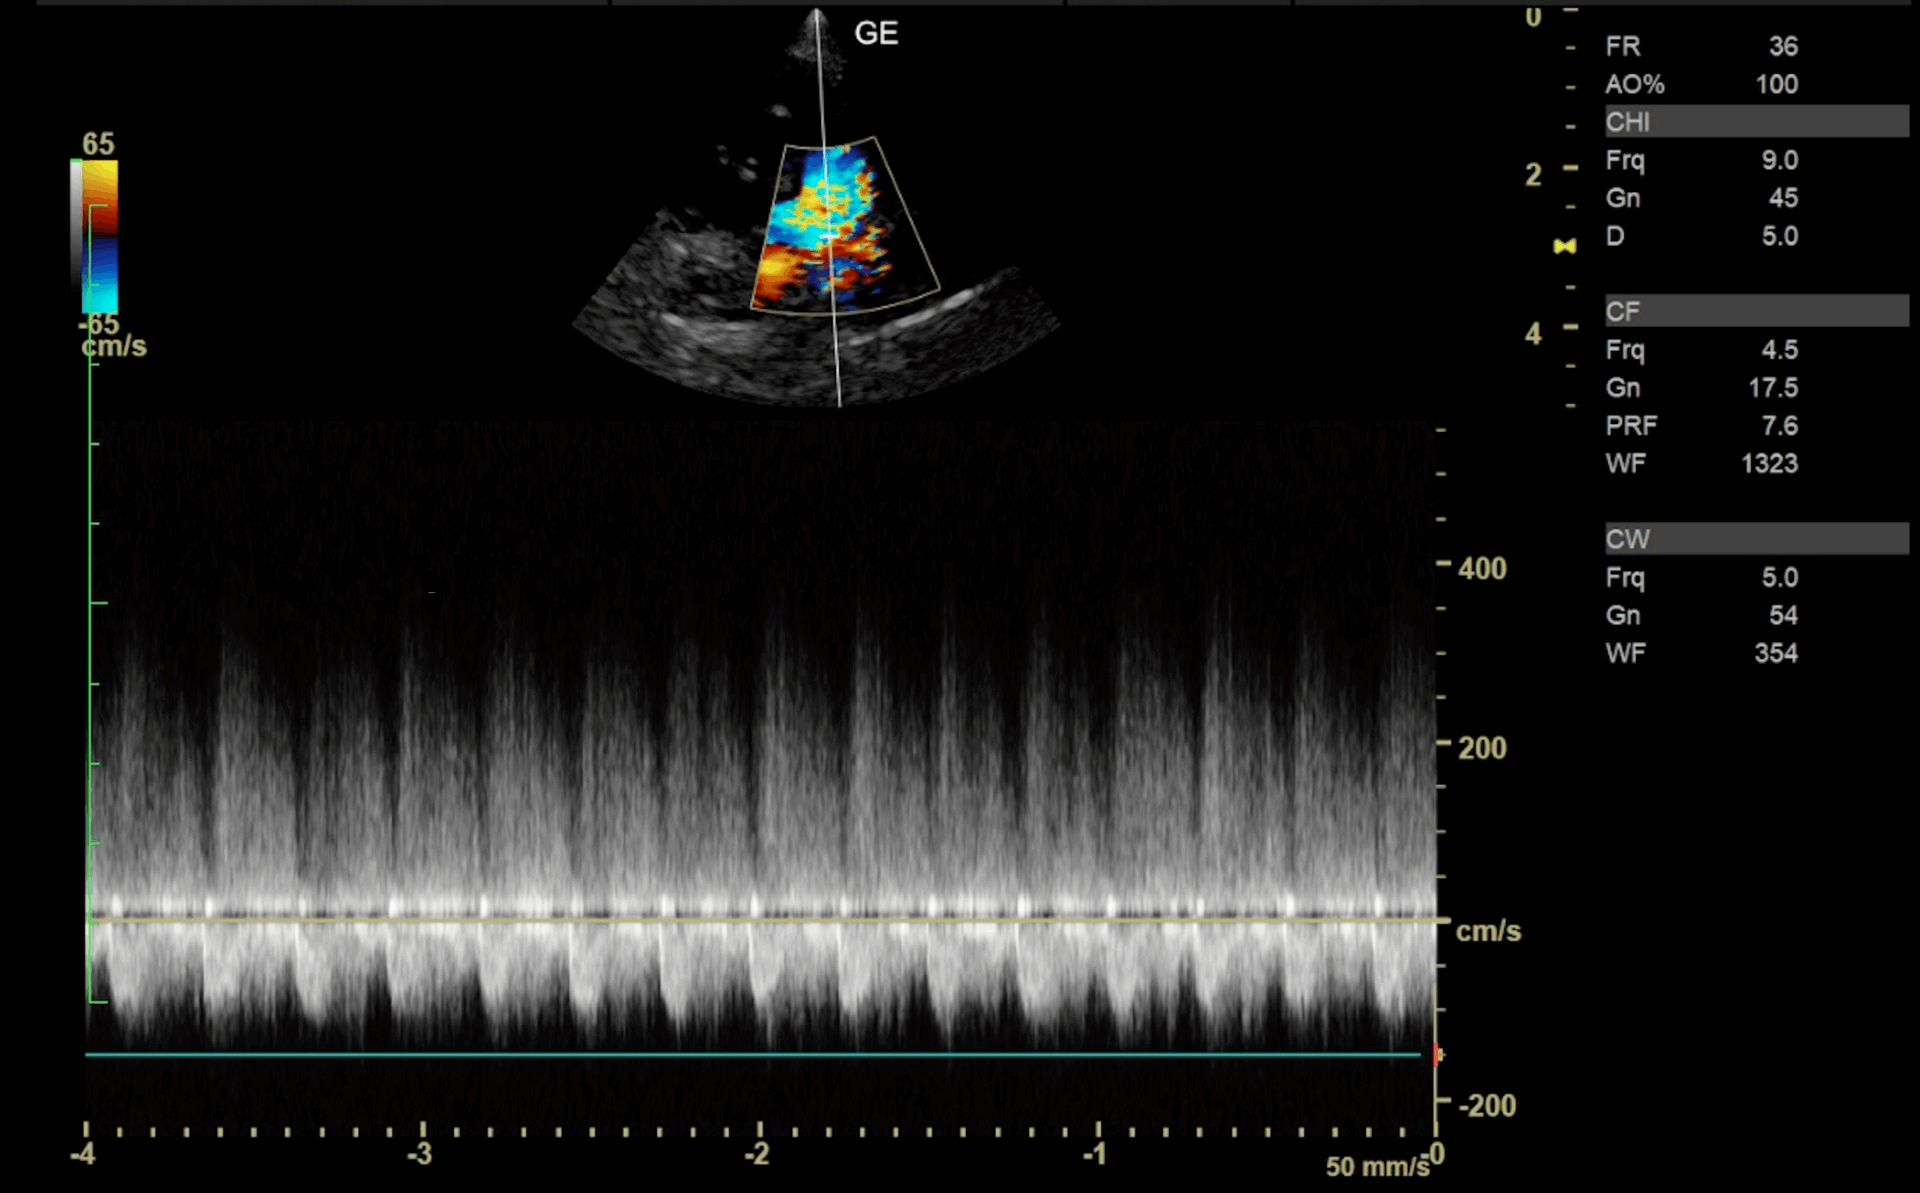

Case8 猫の動脈管開存症

2025年9月26日

胸部外科